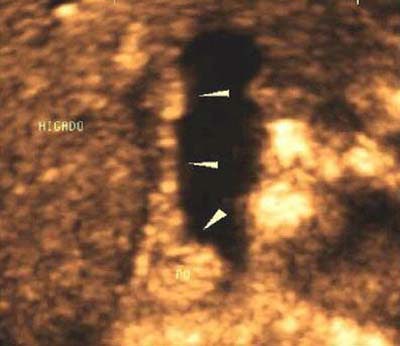

Obstruction of the common bile duct and pancreatic duct by tumoral growth at head of pancreas

A 50-year-old man who developed a greenish jaundice over 15 days, along with general decline in health, was admitted to the ultrasound department for an abdominal scan, assessment of etiology of disease, and treatment. The study showed dilatation of the intrahepatic and extrahepatic bile ducts, with distal obstruction of the common bile duct, tumor at the head of the pancreas, and dilatation of the bile duct and pancreatic duct.

![]() |

| Volumentric reconstructions obtained with 3-D ultrasound (Figure 8a, above) are compared with images obtained using endoscopic retrograde cholangeography (Figure 8b, below). Note the similarity of information that both methods bring to the diagnosis, including tumor at the head of the pancreas, and dilatation of the bile duct and pancreatic duct. |